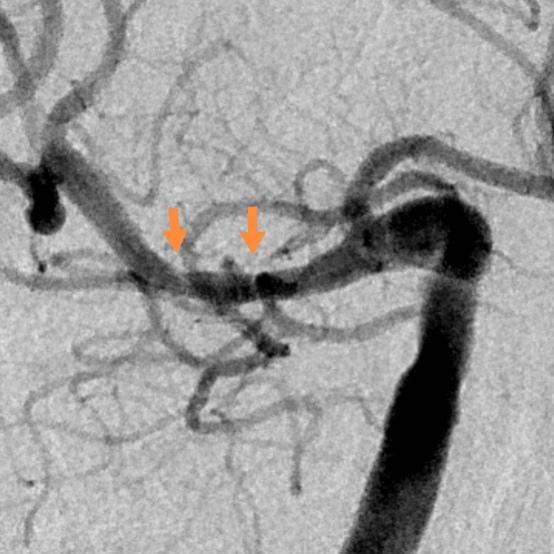

老人家进入医院全面评估后,发现右侧颅内一个主血管存在多节段局限性卡脖子的狭窄,TTP较对侧明显延长,呈缺血状态………,医院多学科讨论评估后,给予第一次外科干预后,患者瘫痪的肢体活动有改善,家人很开心……;在第二次干预之前,又出现了小的新发脑梗塞,继续药物保守治疗,可能还会梗塞;外科干预吧,刚刚出现新发的梗塞,出血风险大,况且又是高龄老年人,血管条件都是个未知数………。本来计划好的二期干预方案受到挑战,面对两难尴尬境地,所有的家人都一时难以决定:向左走?向右走?还是原地踏步进行观望?

最后,手术顺利进行,术后老人家的狭窄完全消除,缺血改善,消除了进一步脑梗塞的风险……,经过术后5天的观察和修整,一切顺利,老人家明天就要出院回家过国庆节啦!